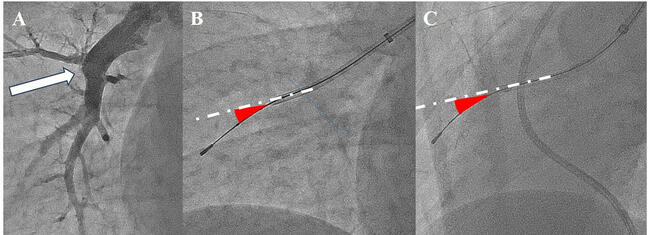

Evaluation of Novel Balloon Pulmonary Angioplasty Using Intravascular Ultrasound for Total Occlusion Lesions and Blood Flow in the Postprocedural Phase After Initially Unsuccessful Procedures

Video Supplement to "Evaluation of Novel Balloon Pulmonary Angioplasty Using Intravascular Ultrasound for Total Occlusion Lesions and Blood Flow in the Postprocedural Phase After Initially Unsuccessful Procedures" (Original Contribution).